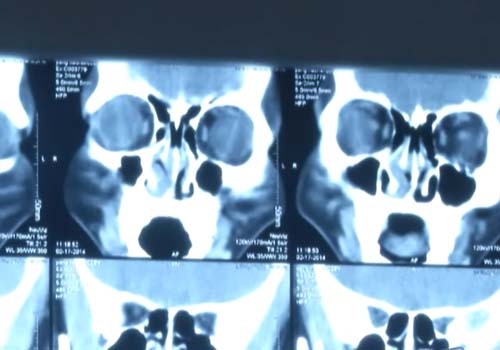

(CT检查结果)

检查项目:鼻内窥镜检查、鼻部CT

检查结果:鼻中隔明显左偏,右侧下鼻甲代偿性肥大妨碍了窦口引流,继而影响了鼻窦。

病情诊断:鼻中隔偏曲、慢性鼻窦炎、鼻甲肥大